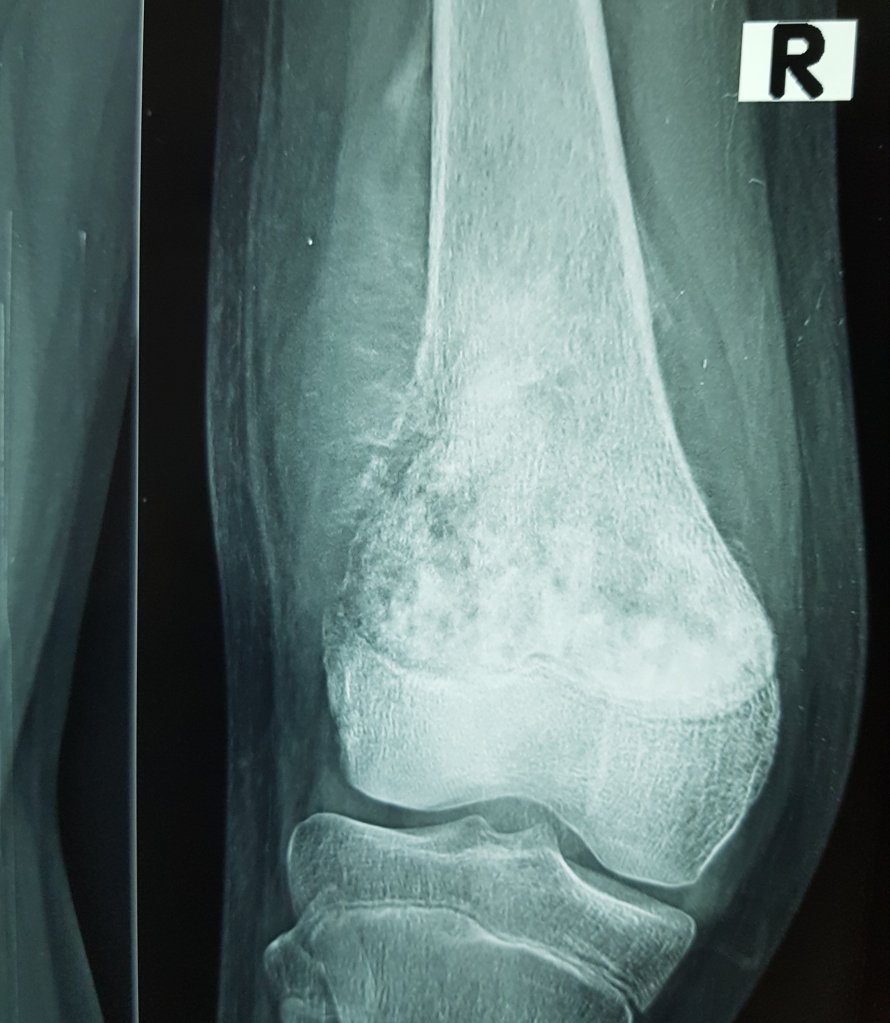

BONE TUMORS (CANCER)

Treatment of all kind of benign and malignant tumors of bones